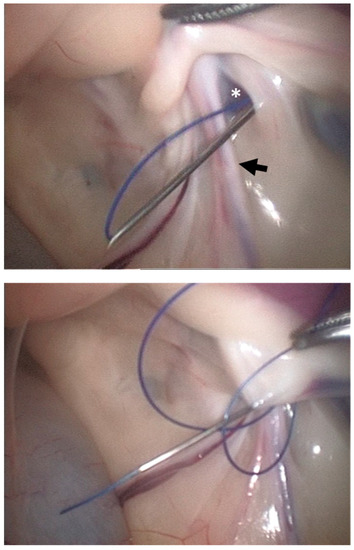

2.1.2. LAPS Surgical Procedure

3.1. Cadaveric Study

3.2. Clinical Cases